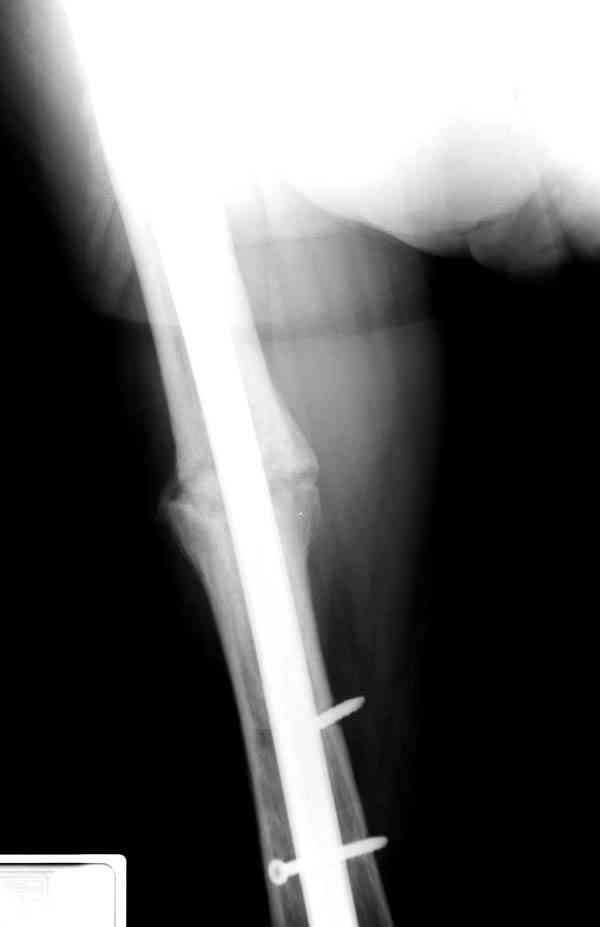

Уважаемые коллеги! У пациента 50-ти лет ложный сустав голени, перелом интрамедуллярного штифта. Перелому около 2 лет, ходить с полной нагрузкой начал через 3 мес. после операции. Боли при ходьбе почувствовал около 2 мес. назад. На данный момент ходит с полной нагрузкой без посторонней опоры. Среди коллег развернулась дискуссия по поводу способа оперативного лечения: -удаление штифта с перештифтовыванием блокированным штифтом с рассверливанием и остеотомией м\б кости -стабилизация зоны ложного сустава по медиальной поверхности LCP-пластиной с декортикацией или без -удаление штифта или без и синтез в АВФ с декотрикацией или без и остеотомией м\б кости

Все перечисленные варианты способны привести к желаемому результату. Несращение здесь - результат нестабильности, так что любой вариант

стабилизации решит проблему. Одного безоговорочно лучшего нет, у всех есть плюсы-минусы.

Наименьший по инвазивности - наложение спицевого аппарата без удаления стержня, с последующей либо дистракцией либо компрессией. Можно и устранить антекурвацию, это тоже создаст стабилизирующее напряжение тканей.

Наиболее быстро достичь опорности без боли и внешних приспособлений - удаление и блокируемый реостеосинтез с рассверливанием. Лучше бы тоже с

восстановлением оси (отклоняющая спица в дистальном отломке, чтобы новый стержень прошел не в старый канал, а кзади от него), еще и для создания дополнительного напряжения тканей в области несращения. Открывать зону несращения не надо.

Периферический отломок стержня - наверно, надо воспользоваться отверстием, над ним сделать трепанацию и через него вверх провести длинную спицу, сделав на ее нижнем конце крючок. Лучше уже перед этим рассверлить центральный отломок.

Сросшаяся малоберцовая как распорка привела к образованию ложного сустава. В таких случаях удаляем сломанный штифт и проводим стимуляцию ложного сустава рассверливанием. Рассверливание канала создает стимуляцию на месте ложного сустава, и динамический вариант блокировки штифта с большим диаметром создаст стабильность. Ранняя нагрузка после остеотомии малоберцовой приведет к сращению ложного сустава.

Приспособление для удаления сломанных штифтов и наличие ЭОП облегчит задачу. При отсутствии крючка тогда можно применить обычный длинный ball pointed guide wire от интрамедулярного набора. Проволока, пропущенная за пределы гвоздя и зажатая другая вытащат сломанный конец штифта без проблем.